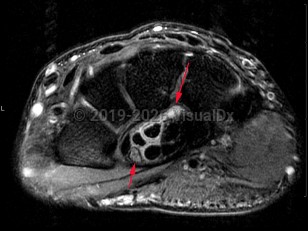

When the bundle of flexor tendons and median nerve in the synovial sheath enter the narrow passageway on the palm side of the wrist and continue between the carpal bones, the nerve (being the softest structure) is most at risk of injury. The median nerve provides sensory innervation to the first three and a half fingers and motor innervation to the lumbricals, opponens, abductor pollicis brevis, and flexor pollicis brevis, the latter 3 muscles making up the bulk of the thenar eminence. When compression occurs within the confined space of the tunnel, the thumb, index, middle, and half the ring fingers develop tingling or numbness. Weakness and atrophy of the thenar eminence can also occur